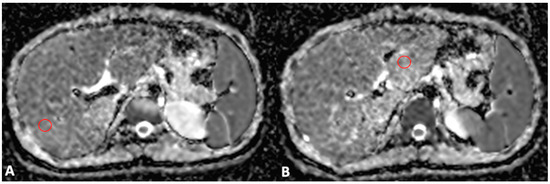

3.2. Magnetic Resonance Imaging